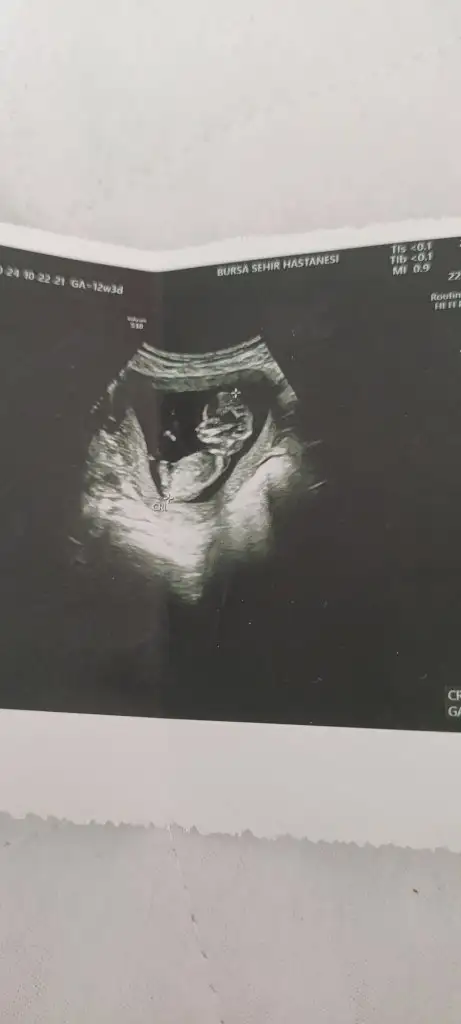

Canim 13 haftalik bakarmisiniz

Eklentiler

• IMG_5071.webp

20,1 KB · Görüntüleme: 33